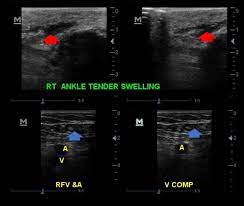

5. Comprehensive Approach to Lower Limb Doppler Ultrasound By Dr. Ekta Mishra

In this detailed and clinically relevant session, Dr. Ekta Mishra takes you through a step-by-step approach to performing and optimising Lower Limb Arterial Doppler Ultrasound. This video is a must-watch for radiologists, sonologists, vascular surgeons, and clinicians involved in peripheral vascular assessments.

Key learning points:

• Fundamentals of Doppler ultrasound physics

• Importance of grayscale optimisation before Doppler application

• Choosing the right probe: high-frequency vs. low-frequency

• Image optimisation techniques: depth, sector width, gain, and frame rate

• Critical role of Doppler angle and how to achieve optimal insonation

• Understanding colour flow patterns, artefacts, and angle correction

Click Here to Watch